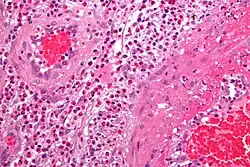

- The definite diagnosis of vasculitis is established after a biopsy of involved organ or tissue, such as skin, sinuses, lung, nerve, brain, and kidney. The biopsy elucidates the pattern of blood vessel inflammation.

- Some types of vasculitis display leukocytoclasis, which is vascular damage caused by nuclear debris from infiltrating neutrophils.[37] It typically presents as palpable purpura.[37] Conditions with leucocytoclasis mainly include hypersensitivity vasculitis (also called leukocytoclastic vasculitis) and cutaneous small-vessel vasculitis (also called cutaneous leukocytoclastic angiitis).